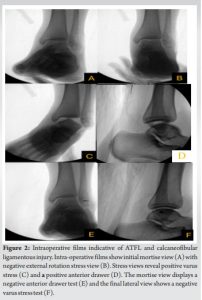

During the operation, an extension of the open traumatic arthrotomy was performed distally to gain exposure to the tibiotalar joint. It was noted that the ATFL, calcaneofibular ligament (CFL), posterior talofibular ligament (PTFL) and the lateral ankle capsule were torn with the talus readily visible. Once exposure was completed, stress examinations were performed showing a negative external rotation stress test but a positive anterior drawer and a positive varus stress test (Fig. 2).

The ankle joint is formed by the distal tibia, fibula, and talus which are stabilized by ligamentous complexes: The tibiofibular syndesmosis (anteroinferior tibiofibular, posteroinferior tibiofibular, and the interosseous tibiofibular ligament), the medial collateral ligaments (superficial and deep deltoid) and the lateral collateral ligaments (anterior talofibular, calcaneofibular, and the PTFL). Given its anatomic location, the ATFL is the main lateral stabilizer of the ankle joint limiting both anterior translation and internal rotation of the talus [5]. Pure ATFL injuries are the most common lower ankle injuries, while ATFL and CFL dual injuries are the second most common [6]. The CFL is rarely injured in isolation because it works in concert with the ATFL to prevent inversion of the ankle; increasing the amount of force the lateral collateral ligaments can withstand [7]. However, a pure ligamentous dislocation has been found to occur with various mechanisms. The most common injury pattern occurs when the ankle is maximally plantar flexed with an axial load combined with forced inversion of the foot. This allows injuries of the ATFL and CFLs leading to a posteromedial dislocation [8]. When recreated by Fernandes in cadaveric studies, it was observed that this injury mechanism can also result in pure medial or lateral dislocation with compromise of the ATFL and CFLs [8]. Although it is more common to observe posteromedial dislocations with ligamentous damage, to the best of our knowledge only a limited number of cases have been published describing a lateral open ligamentous disruption without associated fracture or dislocation. Of these cases, Bryant et al. reported two cases of lateral collateral ligament injuries after extreme inversion during rock climbing, suggesting rock-climbing shoes can cause increased stress on the lateral ligament and capsule, resulting in open injury [9]. Carter et al. and Chun et al. reported instances where similar injuries occurred in basketball players causing complete ligamentous rupture of the ATFL, CFL, and PTFL [2,10]. Thompson et al. described a severe inversion injury needing surgical repair [11]. In these cases, the degree of instability caused by the injury is not well documented, making it difficult to understand the full extent of the injury. As one can see in our case, a complete rupture of the lateral ankle ligaments and ankle capsule can cause significant instability within the ankle that may not be evident on static ankle imaging (Fig. 2). Due to the rarity of this injury, there is no standard treatment protocol. For instance, there have been examples of using external fixation for immobilization due to extensive destruction and stretching of the capsule as described in Carter et al. [10]. Bryant et al. and Chun et al. had success utilizing surgical repair in which they used sutures to repair the damaged ligaments and capsule for restoration of function, which lead to a high rate of return to pre-injury level [2,10,12]. In our case, we demonstrate successful management of this rare open lateral ankle injury without dislocation using non-absorbable suture and suture anchor augmentation to repair the lateral ankle ligaments and capsule, restoring ankle joint stability.